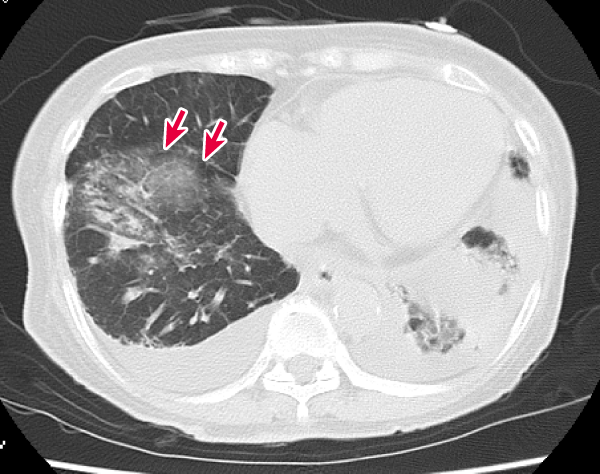

図8 追加で施行した症例の胸部CT